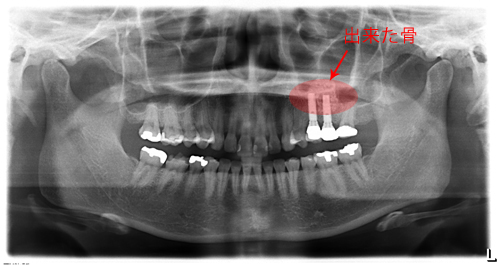

左上の奥歯の骨が少なくてそのままではインプラントを入れられなかったため、オペと同時にサイナスリフトをしました。

今ではしっかり噛めています。骨が極度までない場合でもほとんどがインプラントオペと同時にサイナスリフトが可能です。

奥歯は骨が少なく、骨をつくり、インプラント治療をしました。赤く囲ったところが出来た骨です。